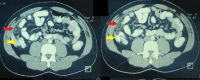

Figure 2. Axial sections of contrast-enhanced CT scan of the abdomen.

The lesion produced by omental infarction (red arrows) can be seen anterior to the ascending colon (yellow arrows).